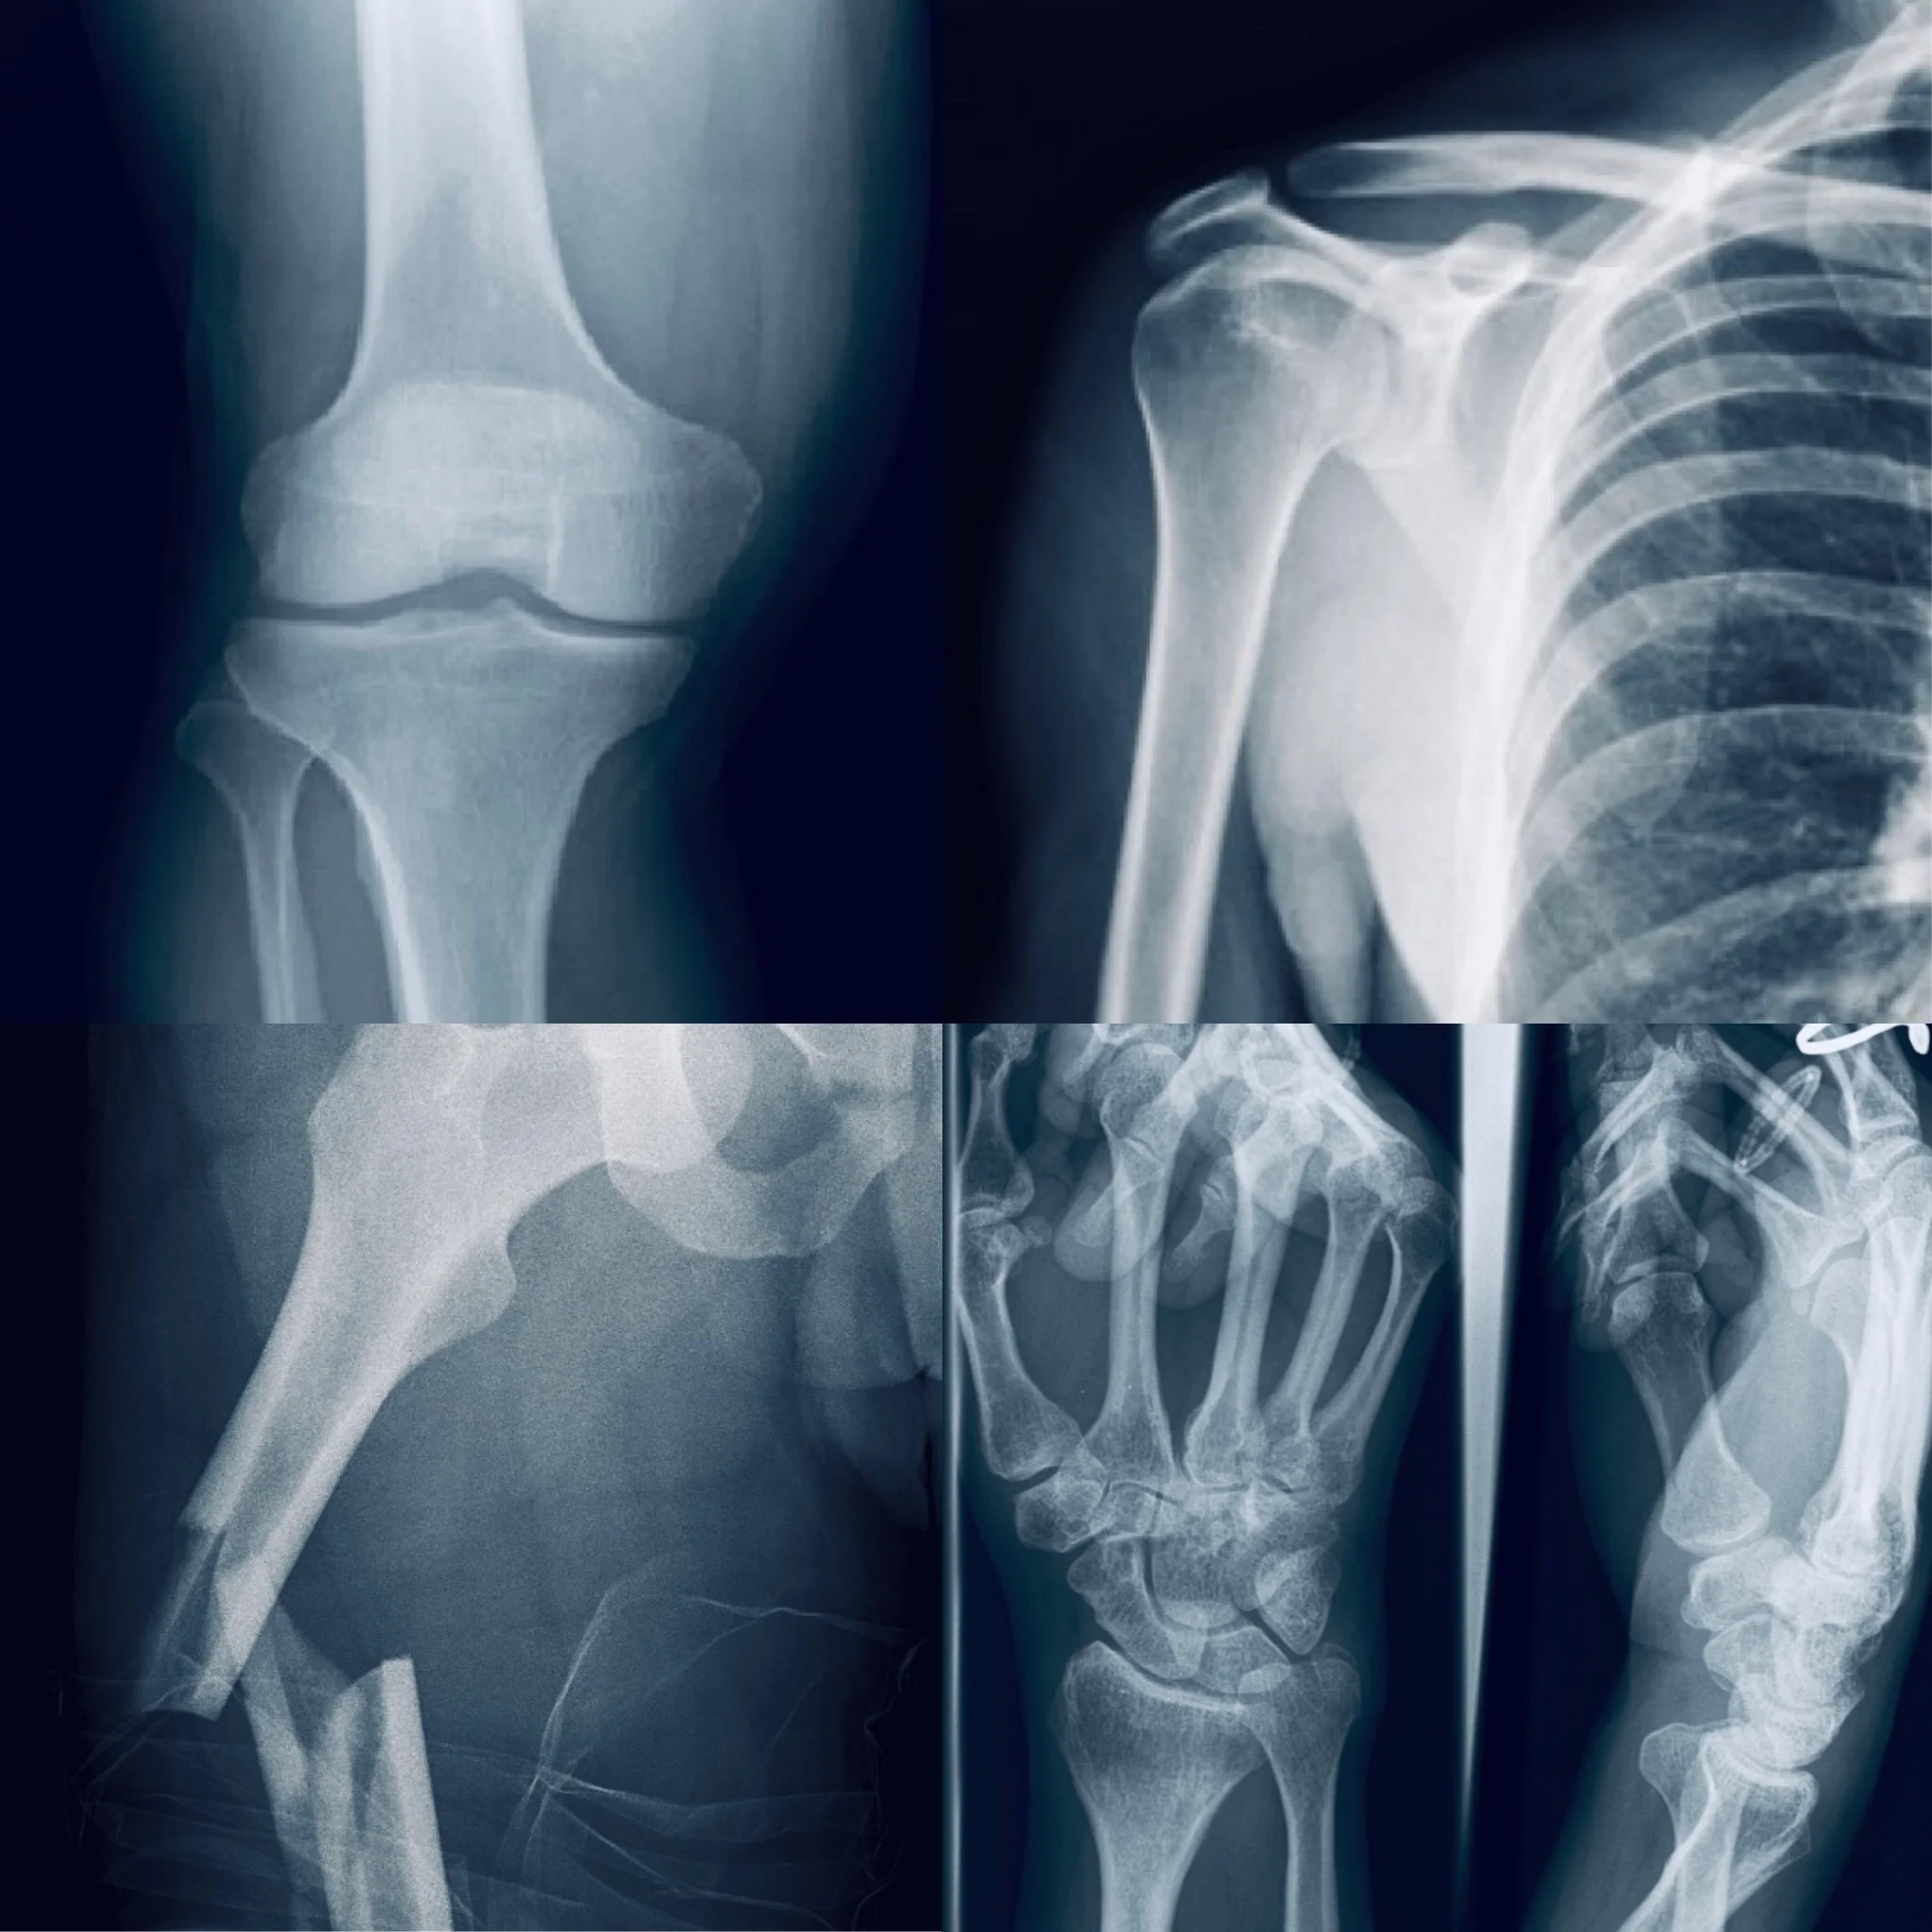

Upper Limb Fractures, Dislocations,

Ligament and Tendon Injuries

Lower Limb Fractures, Dislocations,

Spine Fractures

Paediatric Trauma

Knee Conditions